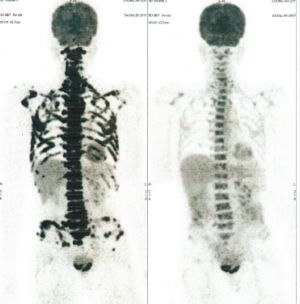

CASE NO: 3 (PROSTATE CANCER)

A middle-aged man with castration resistant prostate cancer, having failed all currently available cancer treatment, was very weak, and getting worse every day. The PET/CT scan showed he had massive bone metastases. After a few treatment, all the bone metastases went into remission. About 6 months later, he is still in remission.

CASE NO: 4 (PROSTATE CANCER)

A middle-aged man with castration resistant prostate cancer and massive bone metastases, failed all currently available cancer treatment, including with the new and expensive drug XTANDI. After a few treatment, most of the bone metastases went into remission, and the remaining ones are less active. Treatment will continue. Cases no: 3 and 4 show that terminal prostate cancer today can be cured with our new cancer treatment.